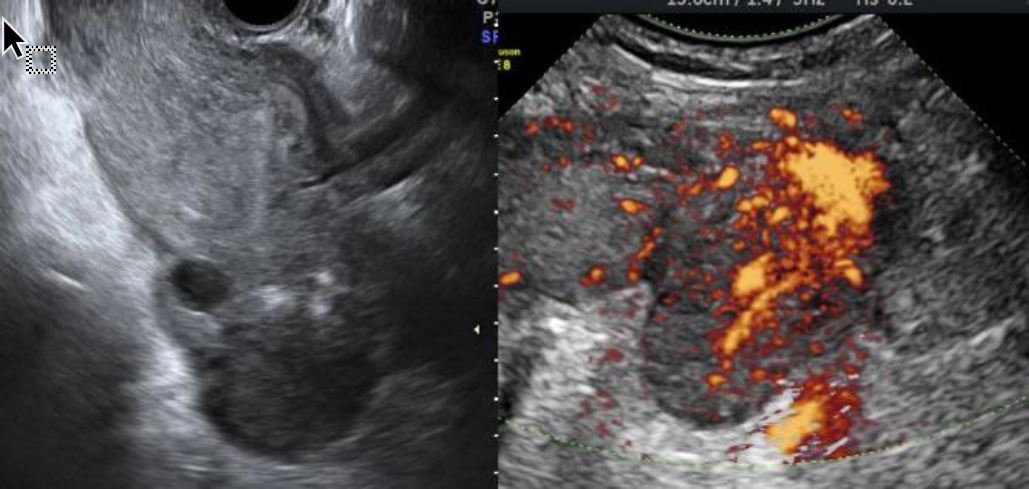

On the 5th postpartum day, she developed fever (maximum tympanic temperature of 39.8°C) and left pelvic pain. No other relevant symptoms or signs were identified. Laboratory assessment showed blood hemoglobin 9.7g/dL, leukocytosis (16,06 x 109/L with 88% neutrophils), elevated C-reactive protein (CRP; 157,5mg/L) and a urinary infection caused by Streptococcus pyogenes (sensitive to penicillin, clindamycin, and trimethoprim-sulfamethoxazole). Ultrasound revealed an endometrial cavity with non-vascularized 14-mm-thick amorphous content, edematous enlarged left ovary, apparently without pathological adnexal formations, and congested ovarian branches originating from left internal iliac artery (Figure 1). The mobilization of the left adnexa by ultrasound probe was very painful. There were no other relevant findings. Angio-CT visualized a vascular pathological process, interpreted as most likely a left ovarian vein thrombophlebitis with a partially permeable lumen (Figure 2). A diffuse densification and very little fluid involving the left ovarian vein (which had a reduced lumen caliber), in association with a small amount of free fluid on the left parieto-colic gutter were observed. The left ovary was large and some reactive para-aortic and primitive iliac lymph nodes were identified (Figure 2).

Figure 1. Sonographic gray-scale and power Doppler findings in patient with ovarian vein thrombosis. Gray-scale image of the left edematous ovary (left). Vascular engorgement (passive hyperemia) within left ovarian parenchyma visualized by power Doppler (right).